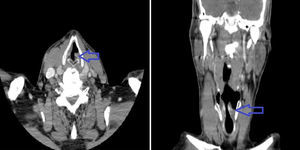

En la TAC craneal no se encontraron datos de afectación vascular cerebral isquémica o hemorrágica. En la TAC cervicotorácica (fig. 1) y abdominal se evidencia parálisis de cuerda vocal izquierda y aneurisma de aorta abdominal a nivel infrarrenal de 47×48mm, sin otros hallazgos.

En la valoración otorrinolaringológica se confirma la parálisis de la cuerda vocal izquierda. No se objetivó alteración oftalmológica. Las pruebas de autoinmunidad en el que se incluyó anticuerpos antinucleares, anticuerpos anticitoplasma del neutrófilo, anticuerpos antifosfolípido, factor reumatoide y anticuerpos antipéptidos citrulinados resultaron negativas, las serologías descartaron enfermedades infecciosas bacterianas como sífilis, enfermedad de Lyme y clamidiosis, además, la PCR de virus herpes 1, 2 y citomegalovirus resultó negativa. Los hemocultivos resultaron negativos.